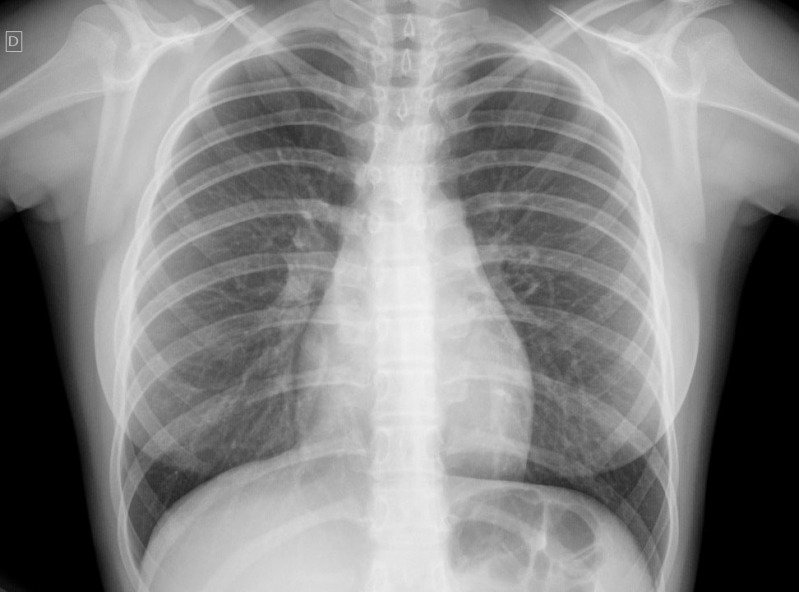

Impressora para Raio-x

RS IMPRESSORASUma impressora para raio-x deve ser específica para que haja o perfeito resultado, principalmente, se houver algum incoveniente que necessita de tratamento. Esse tipo de equipamento é...

Uma impressora para raio-x deve ser específica para que haja o perfeito resultado, principalmente, se houver algum incoveniente que necessita de tratamento. Esse tipo de equipamento é imprescindível em hospitais e clínicas.

Para uma peça de excelência, é de extrema autoridade contar com a ajuda de profissionais especializados e aptos a expandir um serviço de particularidade.

Deseja mais informações sobre impressora para raio-x?

Desenvolvendo um trabalho que oferece comodidade e certificando soluções inovadoras em outsourcing de impressão, a RS Impressoras é consolidada em seu segmento por conta da excelência apresentada em seus serviços.

Priorizando sempre as necessidades dos seus clientes, a empresa conta com uma equipe de profissionais elevadamente qualificados e aptos a expandir um serviço completo e de extrema particularidade.

Com experiencia a começar de 2007, a RS Impressoras garante a satisfação dos seus solicitantes, procurando sempre melhorias em cada um dos seus processos. Saiba mais entrando agora mesmo em contato!

Uma impressora para raio-x deve ser específica para que haja o perfeito resultado, principalmente, se houver algum obstáculo que necessita de tratamento. Esse tipo de equipamento é imprescindível em hospitais e clínicas.

Para uma peça de excelência, é de extrema seriedade contar com a ajuda de profissionais especializados e aptos a ampliar um serviço de particularidade.

Deseja mais informações sobre impressora para raio-x?

Desenvolvendo um trabalho que oferece comodidade e certificando soluções inovadoras em outsourcing de impressão, a RS Impressoras é consolidada em seu segmento por conta da excelência apresentada em seus serviços.

Priorizando sempre as necessidades dos seus clientes, a empresa conta com uma equipe de profissionais elevadamente qualificados e aptos a ampliar um serviço completo e de extrema particularidade.

Com experiencia doravante 2007, a RS Impressoras garante a satisfação dos seus solicitantes, procurando sempre melhorias em cada um dos seus processos. Saiba mais entrando agora mesmo em contato!